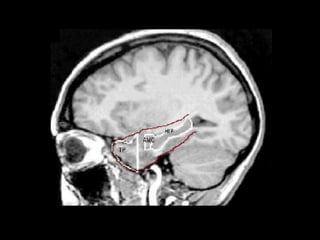

Cross-Section of the Human Brain

Remember the

hypothalamus-

pituitary-adrenal

axis? Hippocampus

Amygdala

Hippocampus

Pituitary

hypothalamus

Thalamus

Area of

and Thalamus

(not shown)

Cross-Section of theHuman Brain Remember the hypothalamus- pituitary-adrenal axis? Hippocampus Amygdala